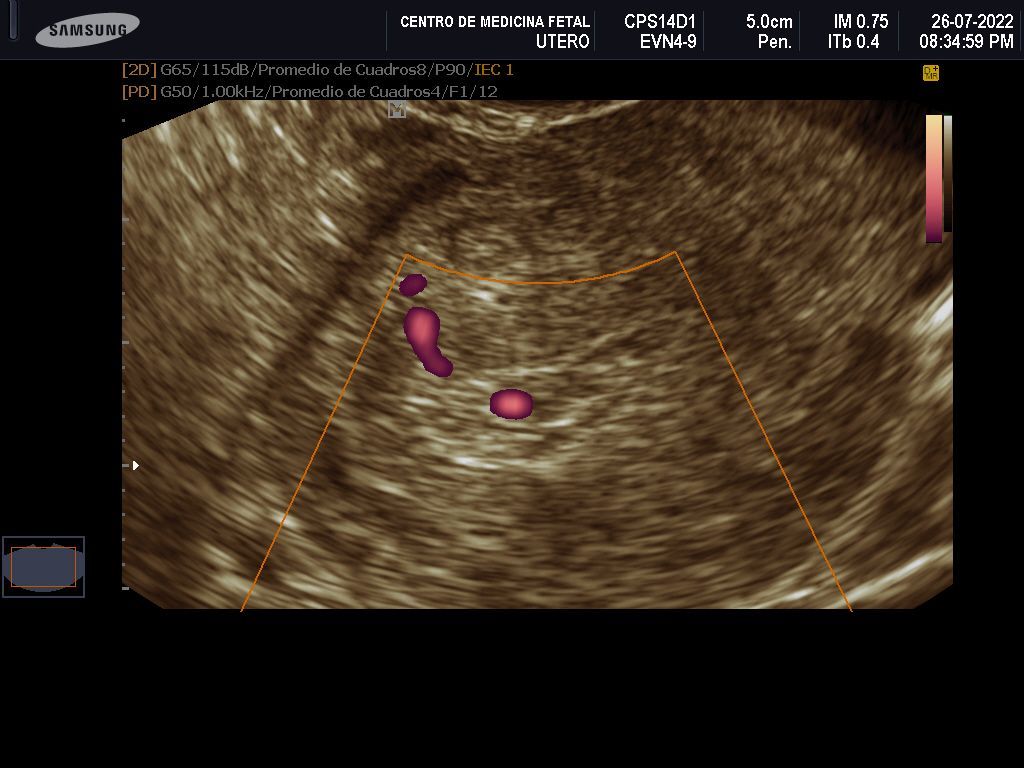

- Detección ecográfica transvaginal o pélvica y tratamiento de: Miomas, quistes de ovario, endometriosis, malformaciones uterinas